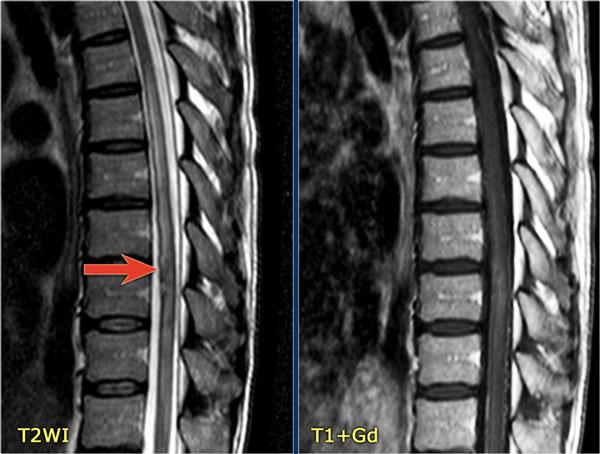

Lưu ý vùng tăng tín hiệu ở đoạn tủy ngực dưới và các mạch máu giãn xung quanh trên chuỗi xung T2W.

Trên chuỗi xung T1W có tiêm thuốc tương phản từ, có hiện tượng ngấm thuốc nhẹ.

Một trường hợp khác với bệnh tủy sống và giãn tĩnh mạch là hậu quả của rò động tĩnh mạch (AVF).

Một bệnh nhân khác với bệnh tủy sống và các mạch máu giãn bao quanh tủy.

Lưu ý các vùng giảm tín hiệu trên chuỗi xung T2W, biểu hiện của xuất huyết.